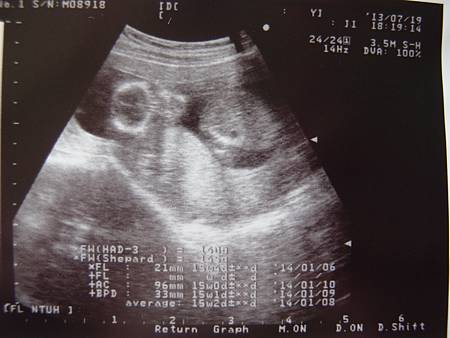

7/19 15W5D

晚上產檢北鼻體重140G,心跳140幾,醫生沒有量一整個身長,只有分開量了頭部,肚子和腿的長度,但是到底量了幾公分我根本都記不得啦!只覺得很開心,只是本來叫老公錄影,但是老公調整相機調了老半天都弄不好,最後甚麼都沒錄到,真是的,老公問醫生說可以知道男生女生嗎?原來醫生已經正在努力照了,但是說北鼻的腳一直擋住,不容易看,我媽從上次就在說應該是女寶包,女生通常都不愛給人家看,後來再照了一下,兩腿之間似乎沒有凸起,所以醫生說70%的可能性是女生,但是要再確定必須是兩個不同時間點來照才能更確定,看來婆婆要有點小失望了,不過回家後老公說上星期婆婆有打電話來說生女生也好啦!希望是真心話囉!畢竟能生出來就偷笑啦!哈哈一直問老公會不會知道是女生他覺得很失望,因為從知道是女寶包後他一直沒有開心的表情說,老公強調他沒有不開心,他只是想到因為我們夫妻倆天生就是皮膚黑的基因,女寶包注定也要天生皮膚黑了,但畢竟她是女生啊!老公覺得女生應該就是要皮膚白纖纖細細的,所以想到這個他就覺得北鼻很可憐,哈哈哈哈哈老公的煩惱真是太好笑啦!